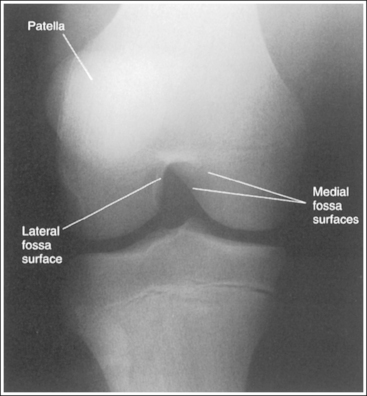

• Analysis of joint space narrowing. On an AP knee projection with adequate positioning, joint space narrowing is evaluated by measuring the medial and lateral aspects of the knee joint, which are also referred to as compartments. The measurement of each of these compartments is obtained by determining the distance between the most distal femoral condylar surface and the posterior condylar margin of the tibia on each side. Comparison of these measurements with each other, with measurements from previous images, or with measurements of the other knee determines joint space narrowing or a valgus or varus deformity. In a valgus deformity the lateral compartment is narrower than the medial compartment; in a varus deformity the medial compartment is narrower (see Images 56 and 57). Precise measurements of the compartments are necessary to ensure early detection of joint space narrowing and are best obtained when the knee joint space is completely open. If an inaccurate central ray angulation was used for an AP knee projection, the knee joint is narrowed or obscured, the intercondylar eminence and tubercles are foreshortened, and the tibial plateau is demonstrated.

The lateral knee compartment is narrower than the medial knee compartment. The patient's knee demonstrates a valgus deformity.

The medial knee compartment is narrower than the lateral knee compartment. The patient's knee demonstrates a varus deformity.